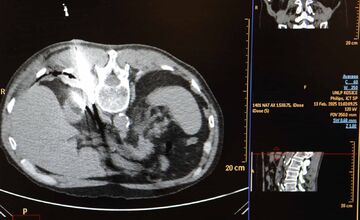

FOTO: Košická univerzitná nemocnica zaviedla pokrokovú liečbu tumorov

VIDEO: Nová nádej pre onkologických pacientov: Unikátna metóda zničí nádor mrazom, využívajú ju aj v Košiciach